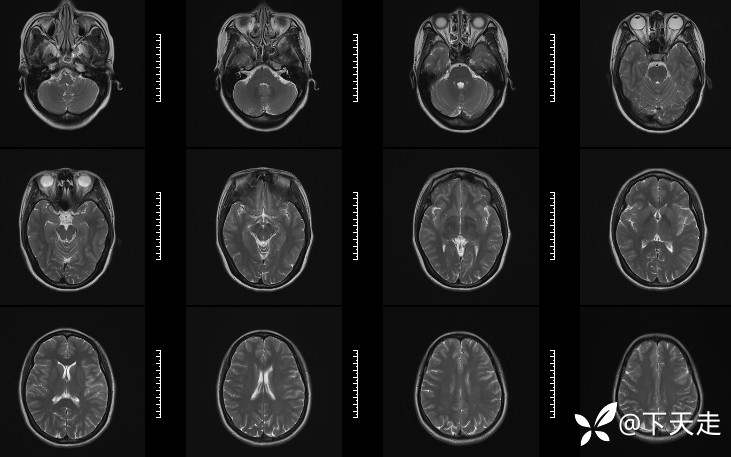

青鹊词 推荐青年女性,37岁,因不能言语就诊于耳鼻喉科,耳鼻喉科医生诊疗后建议神经内科就诊。

查体:神清,完全性运动性失语,四肢肌张力正常,肌力5级。

相关检验检查资料如下